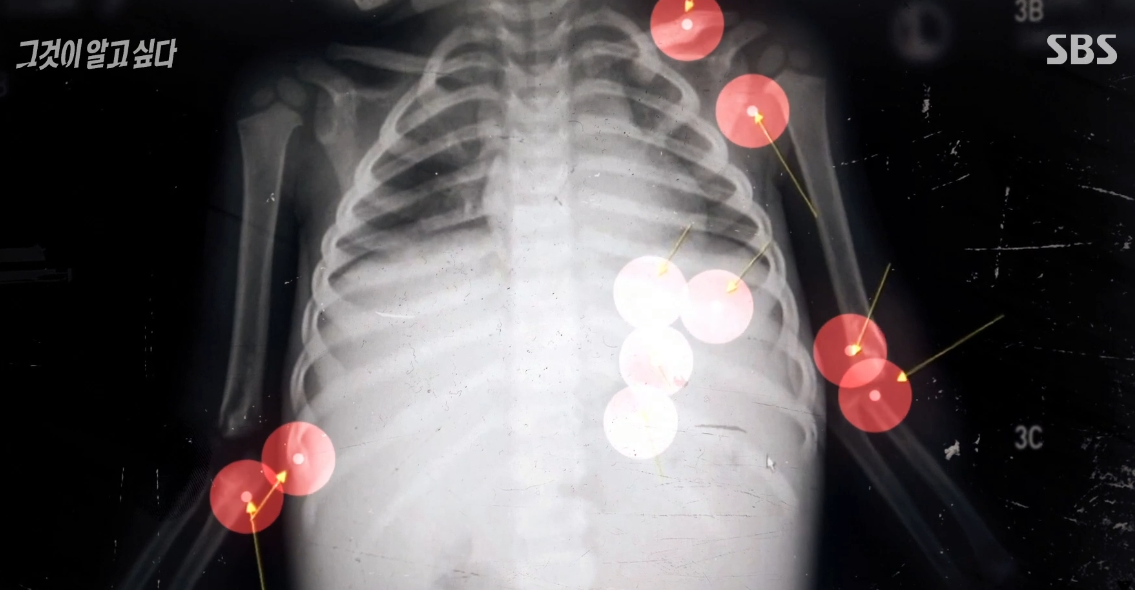

2. 정인이의 신체 곳곳의 골절흔적

후두부, 쇄골 및 대퇴골, 팔, 다리 등에서 10군데 이상의 골절이 보였습니다.

CT 영상에 의하면 정인이의 뱃속은 출혈로 인해 복강 전체가 피로 가득했고,

터진 장에서 빠져나온 공기 일부가 복근 바로 아래, 이미 장기 일부에서 최소 1주일 이전에 충격을 받아 장기가 손상되었다가

회복된 흔적이 보였고, 양팔과 가슴에만 10군데 가량의 골절 유합 흔적 등이 있었습니다.

골절 부위도 쇄골, 갈비뼈, 양쪽 팔꿈치로, 특히 한쪽 팔꿈치의 골절은

방어흔의 일종이거나 성인이 아이의 팔을 잡아 던질 때 주로 생기는 부상이었습니다.

갈비뼈는 외력이 아닌 이상 골절이 흔하지 않은데도, 전면부에 일렬 형태의 연속 골절이 있었습니다.

정인이의 사인 [외력에 의한 복부손상], [췌장 절단 및 후두부와 쇄골, 대퇴골 등이 골절]